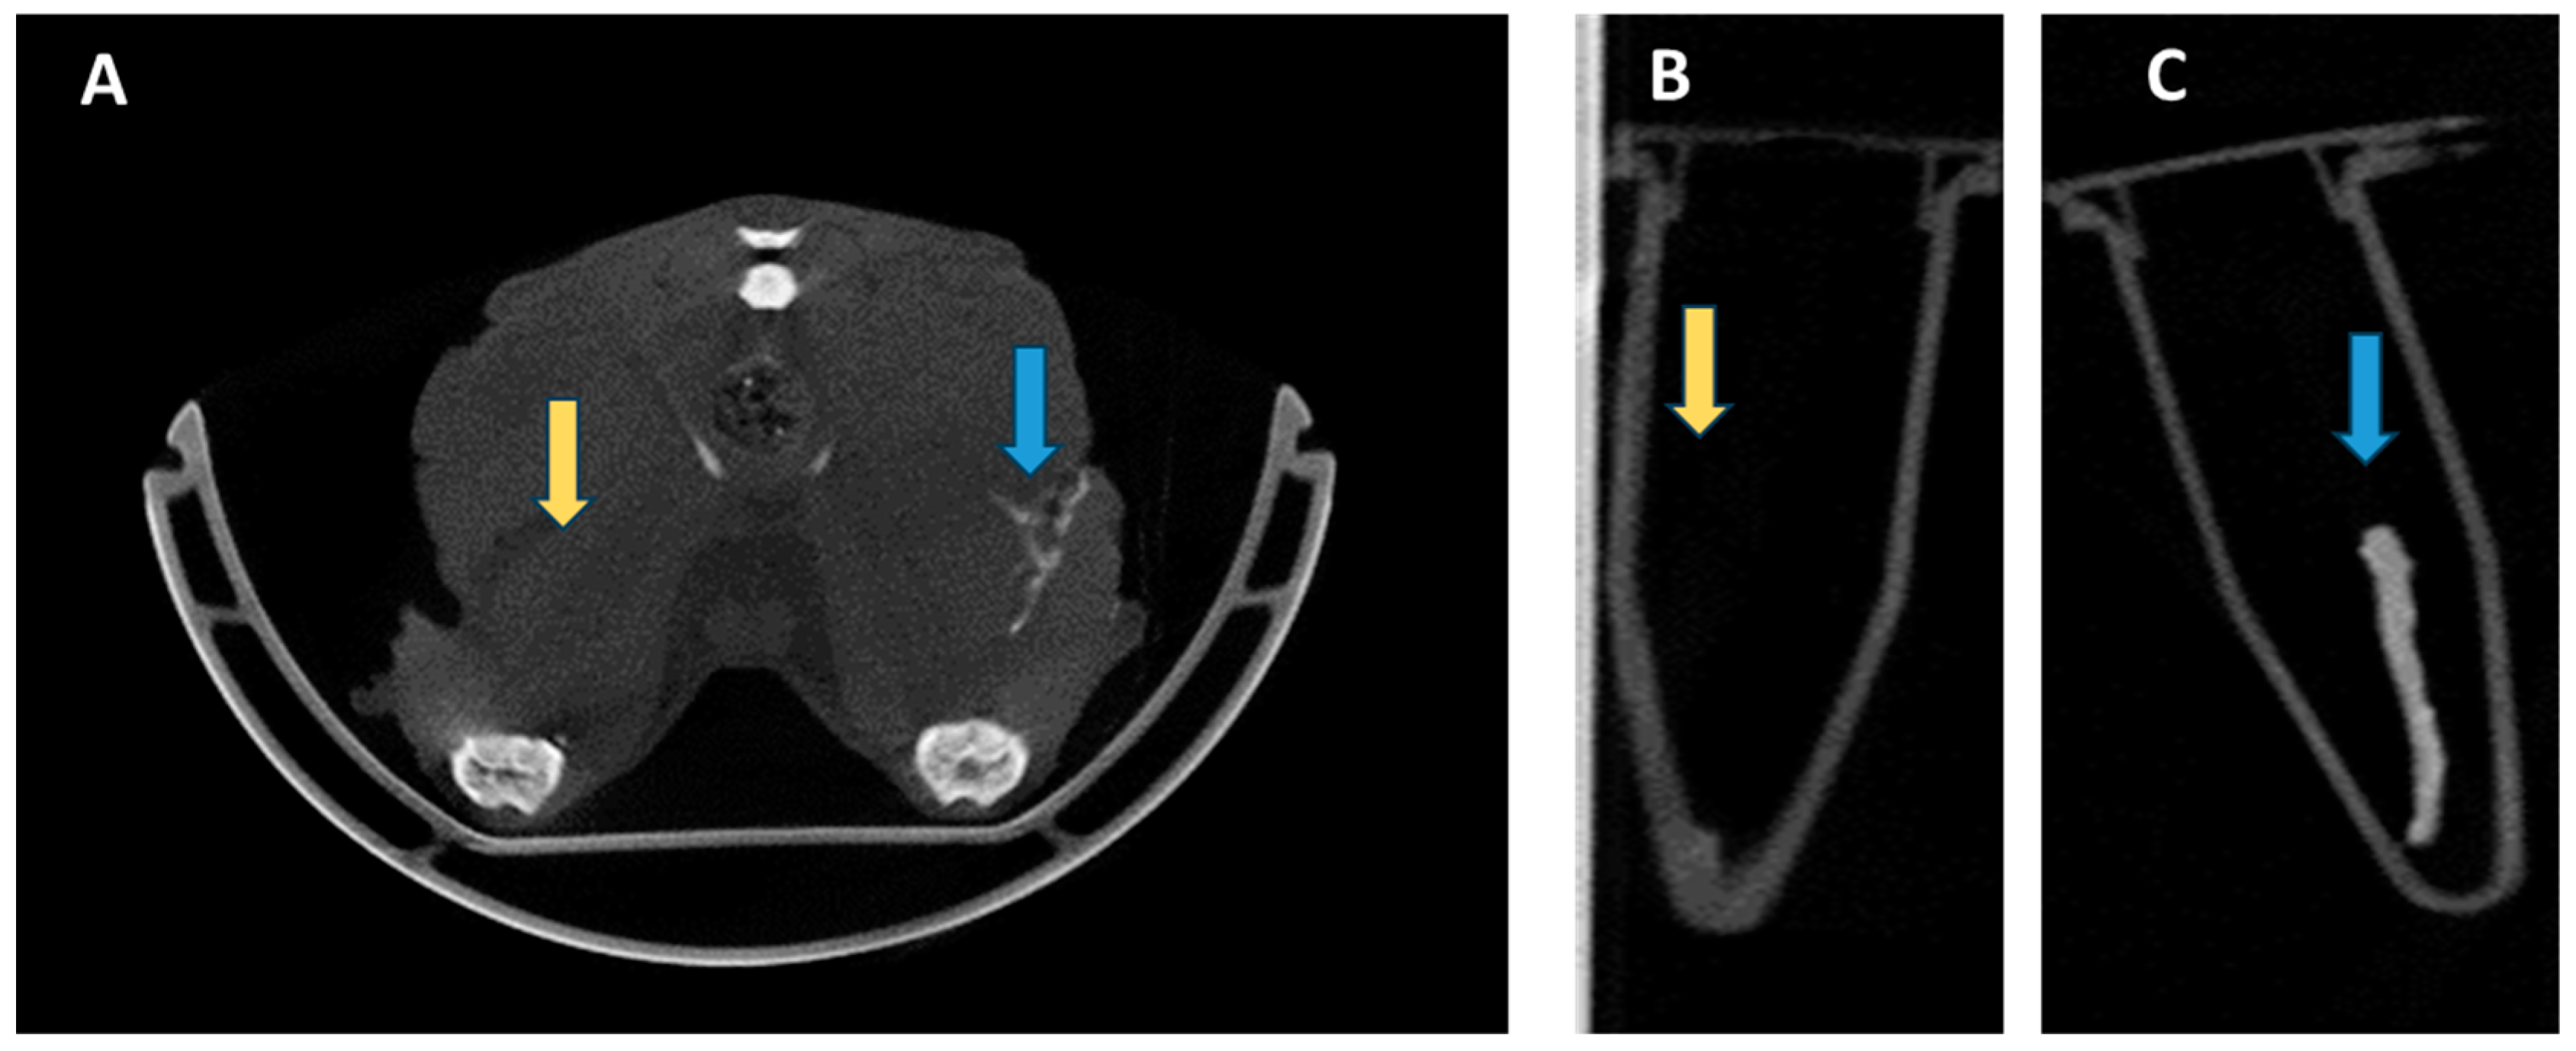

Imaging Peripheral Nerves In Vivo with CT Neurogram Using Novel 2,4,6-Tri-Iodinated Lidocaine Contrast Agent

- McCarthy, J.E.; Serkova, N.J. Computed Tomography Neurography for Visualization of the In Vivo Nervous System: A Proof of Concept. Hand 2024, 19, 931–935. [Google Scholar] [CrossRef]